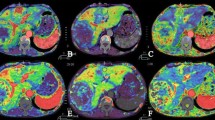

The results on visualization of tumor staining and feeding artery are summarized in Table 2. Sufficient visualization of tumor staining (score, 5–3) was obtained in 18 (60.0%) of 30 HCCs for MIP images and in 11 (37.6%) for VR images; MIP images were significantly superior to VR images (mean rating score, 2.80 ± 1.35 vs. 2.00 ± 1.08; p < 0.001) (Fig. 3). The reason for the poor or absent visualization of tumor staining was insufficient contrast enhancement of the tumors in all (12 for MIP and 19 for VR images). Sufficient visualization of feeding arteries (score, 5–3) was obtained in 28 (93.3%) of 30 HCCs on MIP images; MIP images were significantly superior to VR images (mean rating score, 3.50 ± 0.97 vs. 2.83 ± 1.12; p < 0.001). Visualization was scored as excellent in 21 (70.0%) for MIP images and in 9 (30.0%) for VR images. The reasons for poor or absent visualization of feeding arteries were insufficient contrast of the vessels in all (two HCCs for MIP and three HCCs for VR images).

Images in a 71-year-old man with hepatocellular carcinoma. (A) MIP image and (B) VR image from the left oblique view obtained with contrast material injection in the selective common hepatic artery. MIP image sufficiently reveals the tumor stain (arrowheads) and the feeding artery (arrow); however, the tumor stain was insufficiently visualized on VR image

In our study, although 2D DSA demonstrated tumor staining for all 30 HCCs, MIP images of 3D DSA visualized tumor staining in only 18 (60.0%) of 30 lesions. There are several possible reasons for this result. First, the contrast resolution and signal-to-noise performance of 3D DSA may not be sufficient for visualization of relatively faint staining of tumors in comparison with 2D DSA. Second, since we arbitrarily determined the volume of contrast material and the delay time from the start of the injection, insufficient tumor staining may be related to an insufficient time for a substantial amount of contrast material to reach the tumor during. Further evaluation is necessary to determine the optimal timing of rotational angiography for better visualization of tumor staining. Third, complicated blood supplies of HCCs in underlying cirrhosis from both the portal vein and the hepatic artery may affect the visualization of tumor staining during rotational angiography [21–23].

In this study, two postprocessing algorithms, MIP and VR images, of 3D DSA were compared, and MIP image was superior to VR image for visualization of the tumor staining and feeding artery. The MIP algorithm selects only the voxel with the highest attenuation along a ray projected through the data set, and this characteristic of reconstruction algorithm seems to allow the depiction of low-contrast objects, such as tumor staining and feeding artery down to the subsegmental level. Unlike the MIP image, the VR image is a weighted sum of data from all voxels along lines projected through the data set. Therefore the VR image maintains the original anatomic spatial relationships of the 3D angiographic data set. Although VR image has been reported to be superior to MIP image in demonstrating the interpretation of vascular interrelationships [26, 27], we believe that the MIP image is enough for understanding the anatomic relationship of the hepatic artery branches when the MIP image was analyzed from desired views in real time on the workstation.